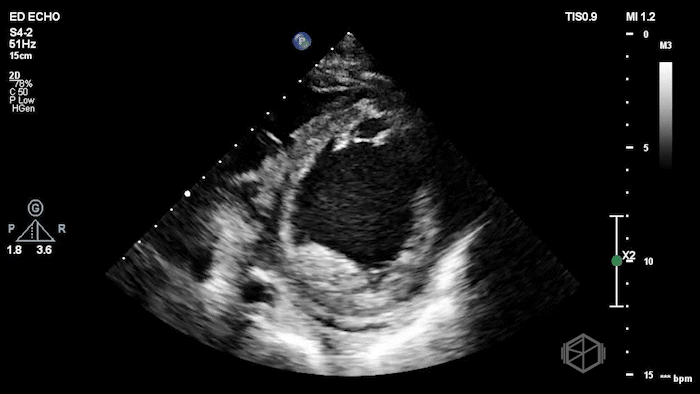

Dr. Herzog was working at NYU Suffolk where he had a mid 60โ€™s female with reportedly only a past medical history of anxiety (recently diagnosed) presenting to the ED with anxious sensation, triaged for anxiety. The patient was slightly tachycardic and mild respiratory distress. Dr. Herzog grabbed the US and saw the following:

The POCUS shows an extremely low EF, about 15-20% visually, with a plethoric IVC. The patient had a cath that showed mild non-obstructive coronary disease and she was determined to have non-ischemic cardiomyopathy due to unknown etiology, possibly viral infection vs. stress related.

Diagnosis: New onset congestive heart failure with significantly reduced ejection fraction.